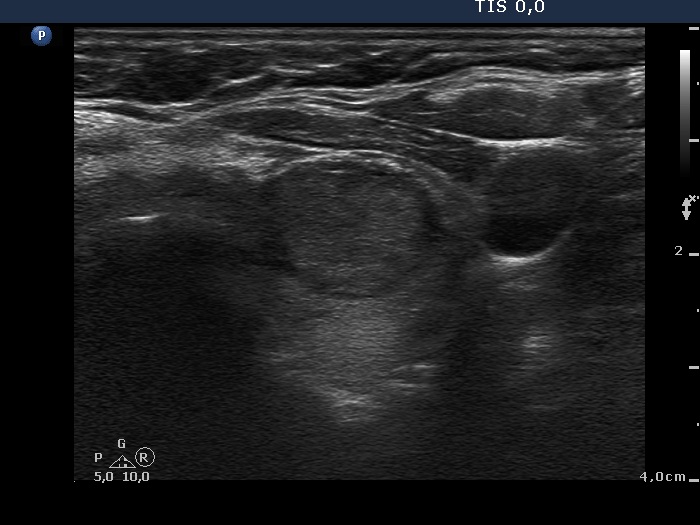

Ultrasonography. The thyroid was moderately hypoechogenic and inhomogeneous. There were multiple echonormal and minimally hypoechogenic discrete lesions in both lobes. Except for the one lesion in the left lobe, these did not correspond to nodule in a pathological sense, while in the event of a minimally hypoechogenic lesion in the left lobe, this possibility could not be excluded.

The patient had a deceptive ultrasound presentation on which the possibility of nodules in a pathological sense could not be excluded. It is worth analyzing the ultrasound images and video.